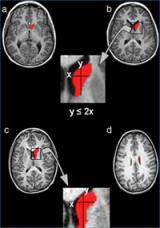

En vermell està pintat el nucli caudat, a la part superior el cap i a la part inferior el cos. La fórmula indica el mètode per separar el cap del cos.

El primer estudi citat pel “Consensus report” va ser publicat l’any 2008 a la revista Psychiatry Research: Neuroimaging. El grup va fixar la seva investigació en el nucli caudat, una de les principals estructures cerebrals involucrades en l’aprenentage i la memòria, que té tres parts: el cap, el cos i la cua. S’havia comprovat que el nucli caudat estava alterat en els pacients amb TDAH, tot i que la literatura prèvia presentava resultats contradictoris sobre quines eren les alteracions concretes. El grup del Dr Vilarroya va descobrir que els pacients amb TDAH presentaven una alteració entre el cap i el cos del nucli caudat que no es veia en els subjectes controls. Amb el desenvolupament d’un nou mètode de segmentació del nucli caudat, entre el cap i el cos es va poder mostrar que els pacients amb TDAH presentaven un nucli caudat dret més petit, fonamentalment degut a una disminució en el cos, que no el cap, del nucli caudat.

Els estudis posteriors han anat dirigits a automatitzar el mètode de segmentació del nucli caudat entre cap i cos per permetre un ús clínic ràpid i eficient. En aquest sentit, s’han publicat dos treballs, un a la revista Biomedical Engineering Online (2011), on els investigadors han desenvolupat un mètode automatitzat de segmentació del nucli caudat, basat en anàlisi d'imatge mèdica i tècniques d’aprenentatge automàtic, i l’altre a la revista Computerized Medical Imaging and Graphics (2012), on els investigadors han optimitzat aquest mètode per poder separar el cap del cos del nucli caudat, obtenint resultats molt similars als de la segmentació manual. Aquests nous mètodes permeten caracteritzar de manera precisa i més ràpida les principals estructures cerebrals, a la vegada que analitzar i fer un diagnòstic precoç del TDAH.